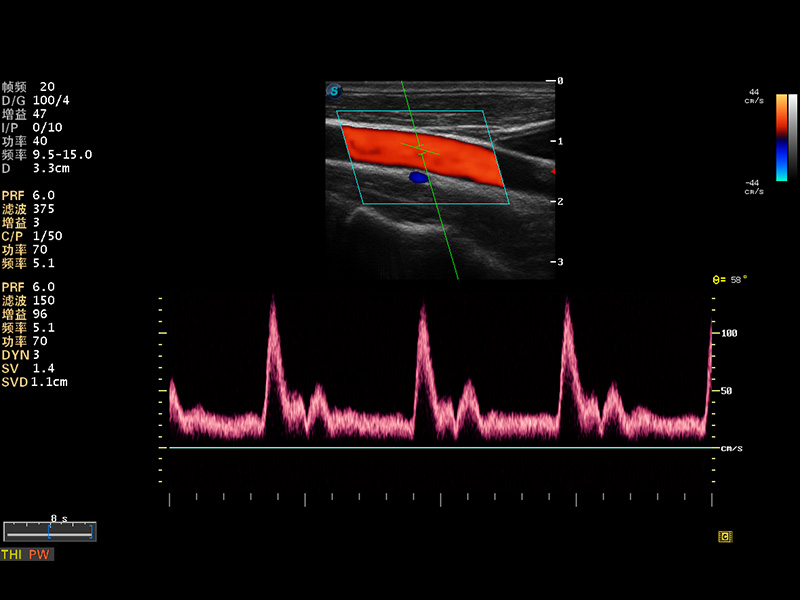

多波束形成器

谐波成像